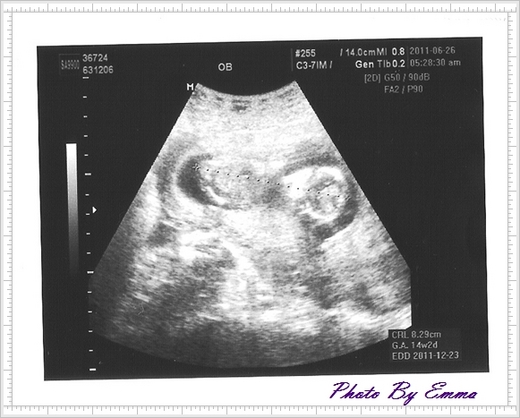

瞧瞧你...14週又2天囉...8.29公分...

小手小腳在媽咪的肚子裡游呀游...真是活潑...